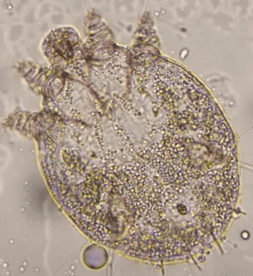

옴의 특징적인 증상과 병변이 보인다면, 검사를 진행하게 됩니다. 검사 방법은 병변을 긁어 현미경으로 옴 진드기를 확인하는 방법 (Mite exam)으로 이루어집니다. 현미경을 통해 아래 사진처럼 옴 진드기가 확인 되면 확진할 수 있습니다.